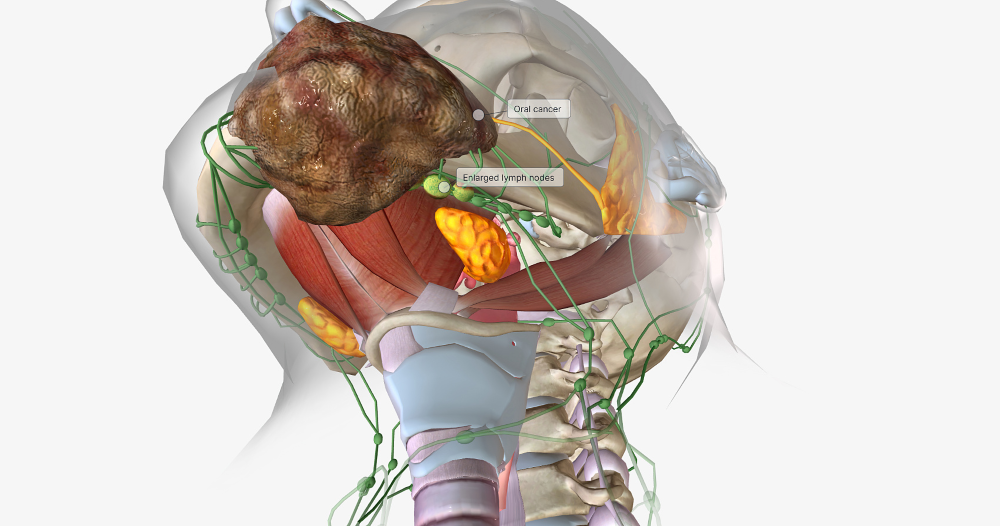

【昆明医科肿瘤医院】口腔肿瘤的心理影响

口腔肿瘤的诊断和治疗过程可能对患者的心理健康产生影响。以下是口腔肿瘤可能对患者心理健康产生的影响。患者情绪低落被诊断为口腔肿瘤可能会对患者的情绪产生负面影响。患者可能会感到害怕、沮丧和无助。他们可能会担心自己的生命和未来,同时还需要应对治疗的压力和不确定性。这...